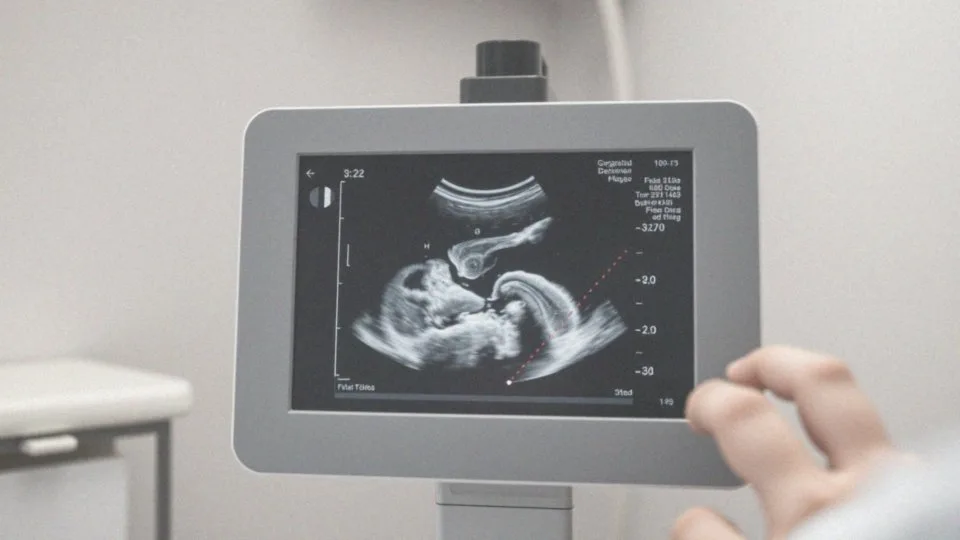

USG genetyczne to badanie prenatalne, które umożliwia dokładną ocenę rozwoju płodu w trójwymiarze. Zwykle realizowane jest w pierwszym trymestrze ciąży, pomiędzy 11. a 14. tygodniem, co czyni je odpowiednim dla przyszłych mam. Jest to badanie bezinwazyjne i bezbolesne, co zapewnia komfort pacjentkom.

W porównaniu do standardowego USG, USG genetyczne zapewnia znacznie wyższą precyzję, co jest niezwykle ważne dla diagnostyki prenatalnej. Dzięki niemu możliwe jest wczesne wykrycie ewentualnych wad rozwojowych. Podczas badania lekarze biorą pod uwagę różnorodne parametry, takie jak:

Badanie USG genetyczne odbywa się zgodnie z ustalonym schematem. Proces rozpoczyna się od krótkiej rozmowy lekarza z pacjentką, podczas której medyk tłumaczy cel badania i odpowiada na wszelkie pytania. Następnie pacjentka zajmuje wygodną pozycję na leżance, a lekarz nakłada na jej brzuch żel ultradźwiękowy. Badanie przeprowadza się przez powłoki brzuszne, co umożliwia uzyskanie wyraźnych obrazów płodu.

W trakcie USG specjalista ocenia istotne parametry, takie jak:

- długość ciemieniowo-siedzeniowa płodu,

- przezierność fałdu karkowego,

- akcję serca zarodka,

- obecność kości nosowej.